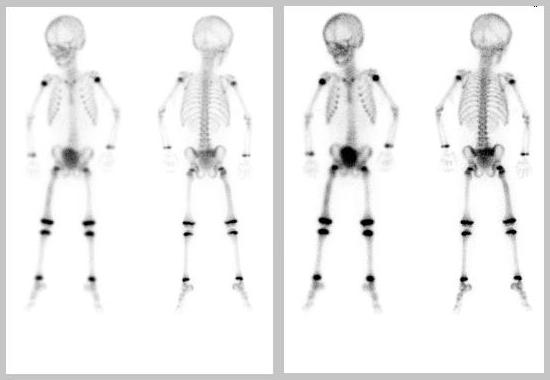

The patient is a 2-year-old male with a right proximal femur mass consistent with Ewing sarcoma. The patient is referred for evaluation of possible distant metastatic disease.

Initial Bone Scan

Three Months Later

Second Scan: There is mild increased tracer activity observed in right femur.

1. Ewing sarcoma of the right femur with a fracture at the proximal femur.

2. No focus of increased tracer uptake is identified that would be consistent with osseous metastasis.

1. Increased tracer activity throughout the entire right femur consistent with the patient's Ewing sarcoma. When compared with the prior study, tracer uptake is diminished consistent with favorable response to treatment.